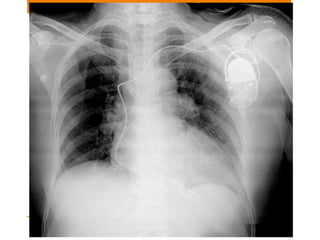

Endotracheal tube • USE:Assisted ventilation • The tip of an ETT will be in a satisfactory position if it approximates to the level of the medial ends of the clavicles • Ideal position is 5–7 cm above an adult’s carina when the head is held in the neutral position. • And if carina is not visible in 95% people it is situated at T5-T7 vertebra

Position changes • TheETT can move up or down • Flex the neck and the tip can move 1.9 cm I,e ~2cm downwards. • Extend the neck and it can move 1.9 cm I,e ~2cm upwards. • Rotate the neck and it can move 0.7 cm upwards.

Malposition • Tip ofright main bronchus: 1. Left lung collapse 2. Right upper lobe collapse 3. Right lung overdistension/pneumothorax • Tip in Oesophagus: 1. ETT lateral to tracheal air shadow 2. Oesophagus distended with air 3. Stomach distended with air